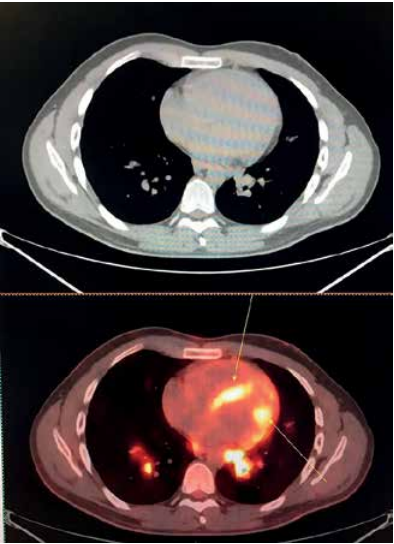

Компьютерная томография (КТ) – один из самых важных инструментов в пульмонологии. Она позволяет получить детальные изображения легких и выявить различные патологии. Однако анализ КТ – трудоемкий и времязатратный процесс, требующий от врачей высокой квалификации и опыта. Даже самые опытные врачи могут упустить небольшие детали или допустить ошибки при интерпретации изображений.

ИИ меняет правила игры в анализе КТ. Нейросети, обученные на тысячах изображений КТ, способны автоматически анализировать снимки и выявлять различные патологии, такие как узелки, опухоли, воспалительные процессы и другие изменения в легких. ИИ может не только обнаруживать патологии, но и измерять их размеры, определять их форму и структуру, а также отслеживать их динамику со временем. Это позволяет врачам получать более полную и объективную информацию о состоянии легких пациента и принимать обоснованные решения о тактике лечения.

Мелкие узелки в легких – один из самых ранних признаков рака легких. Однако обнаружение и идентификация мелких узелков – сложная задача, так как они могут быть очень маленькими и незаметными на изображениях КТ. ИИ способен обнаруживать даже самые мелкие узелки в легких с высокой точностью, что позволяет врачам выявлять рак легких на ранних стадиях, когда лечение наиболее эффективно. ИИ также может помочь врачам в оценке риска злокачественности узелков и в принятии решений о необходимости дальнейшего обследования и лечения.